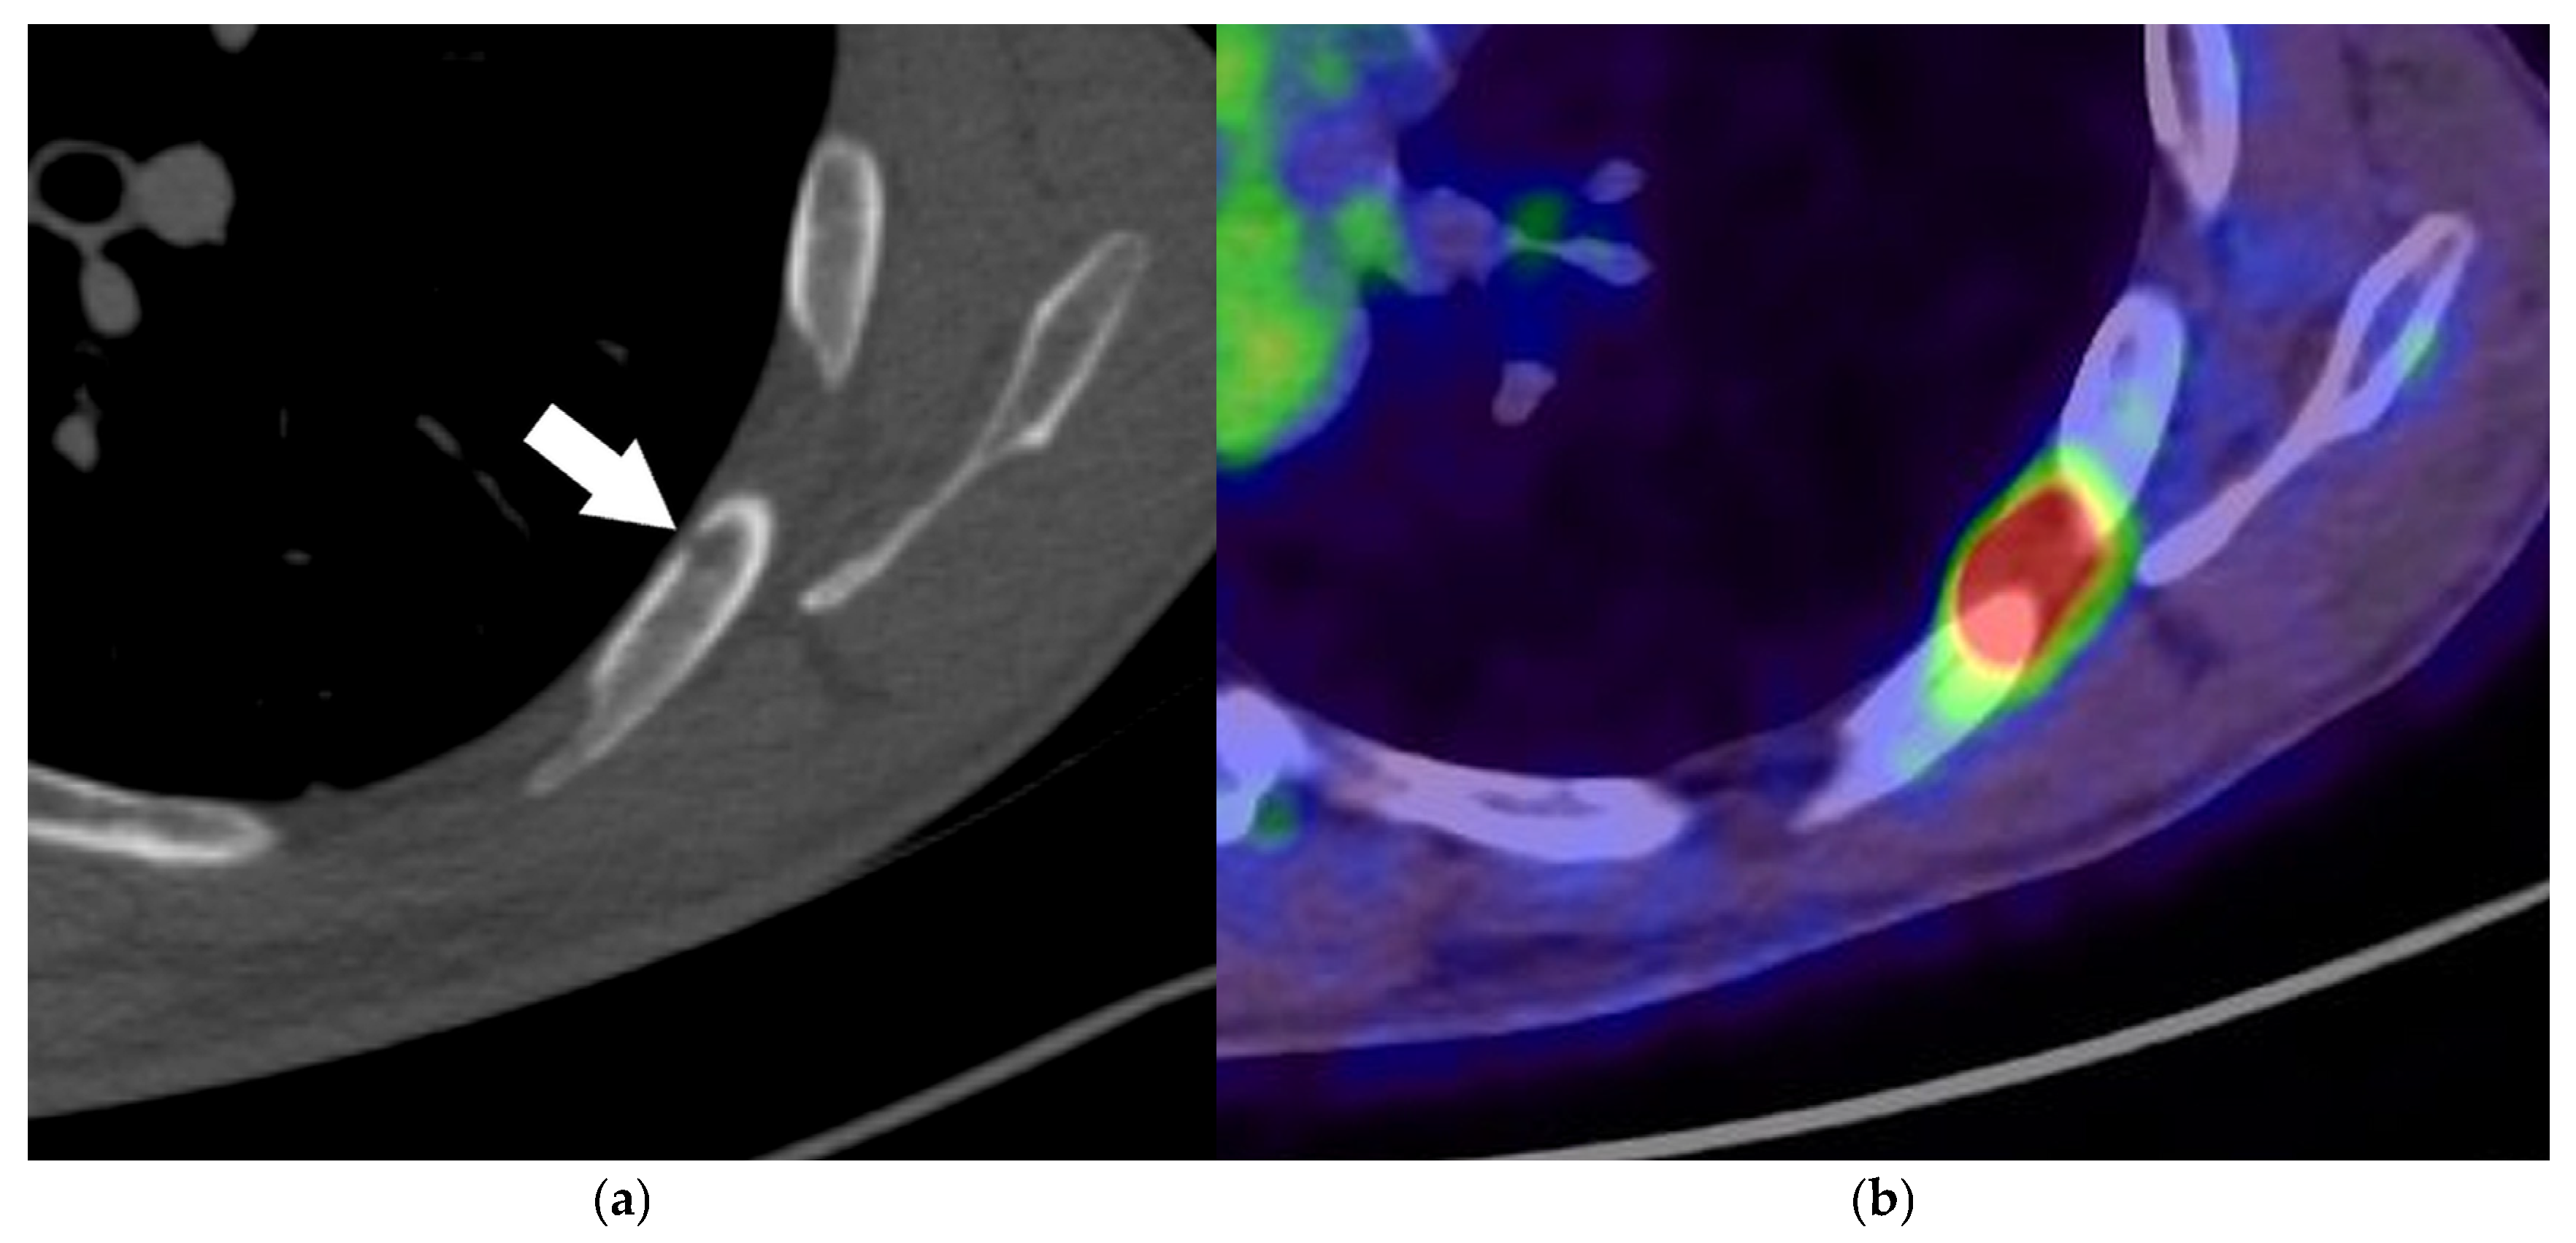

| T2a | Tumor > 3 cm but ≤4 cm in the greatest dimension Invasion of visceral pleura Invasion of an adjacent lobe Involvement of the main bronchus (up to but not including the carina) Tumor associated with atelectasis or obstructive pneumonitis extending to the hilar region, involving either a part of or the entire lung | Visceral pleural invasion should be considered for pleural-attached nodules and pleural-tag nodules [40] PET/CT can better differentiate the obstructing tumor from the tumor-associated atelectasis than CT [26,37] |

| T3 | Tumor > 5 cm but ≤7 cm in the greatest dimension Invasion of parietal pleura or chest wall Invasion of the pericardium, phrenic nerve, or azygos vein Invasion of thoracic nerve roots (T1, T2) or stellate ganglion Separate tumor nodule(s) in the same lobe as the primary | The degree of mediastinal penetration by the tumor needed to invade these T3 structures is not counted as T4 [30] |